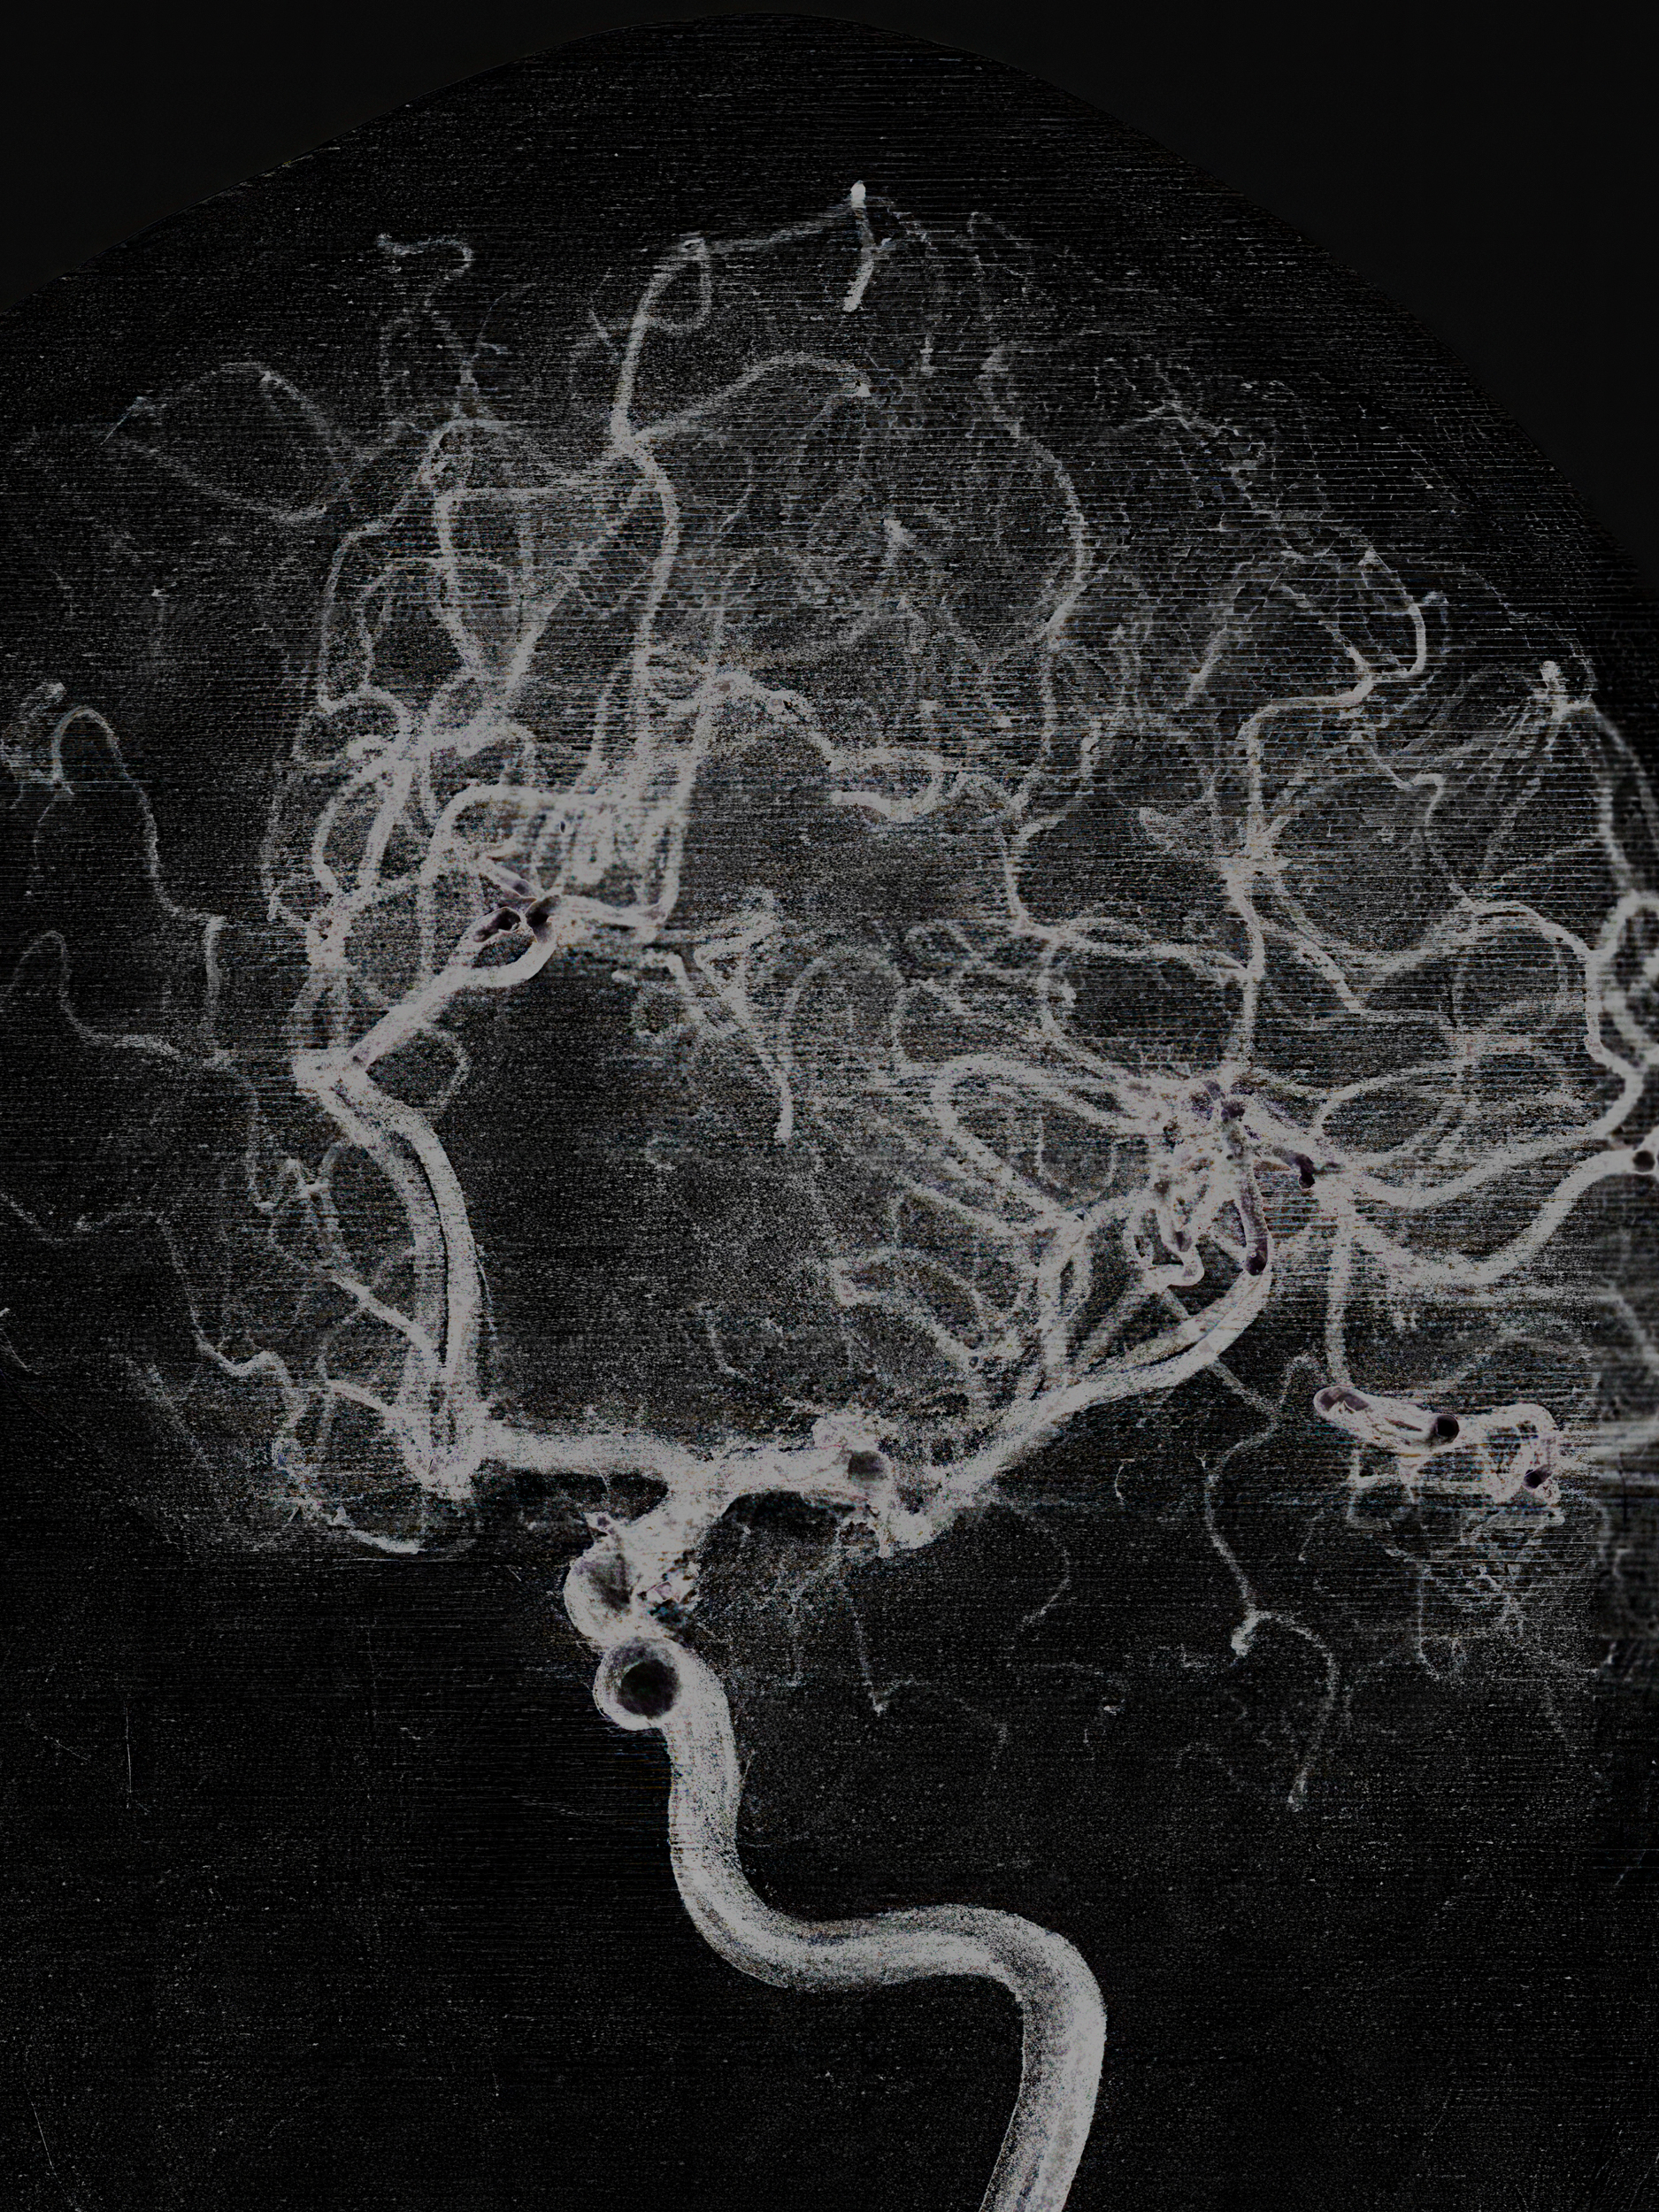

Convolutions

(2023 - ongoing)